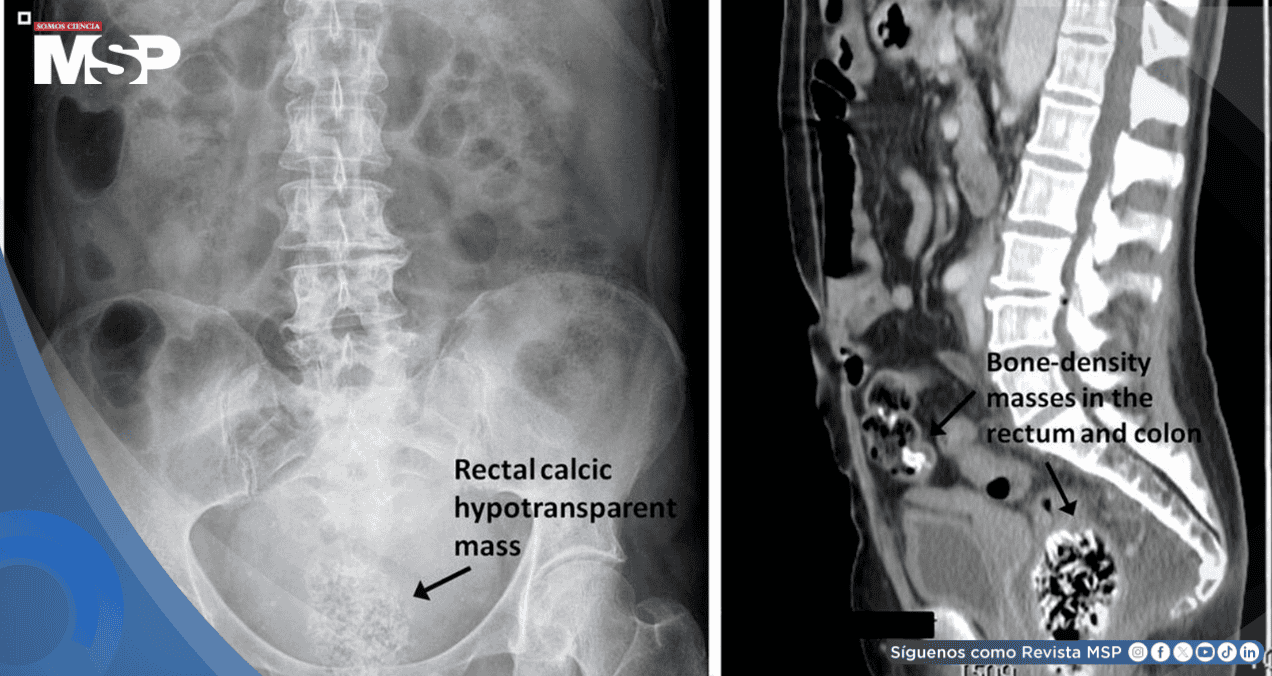

Los estudios de laboratorio no mostraron alteraciones significativas. Las imágenes abdominales confirmaron una importante carga fecal a nivel rectal, mientras que la ecografía transabdominal en el punto de atención evidenció una masa ecogénica densa ocupando el recto.

Con estos hallazgos se estableció el diagnóstico de bezoar rectal masivo compuesto por semillas de calabaza.